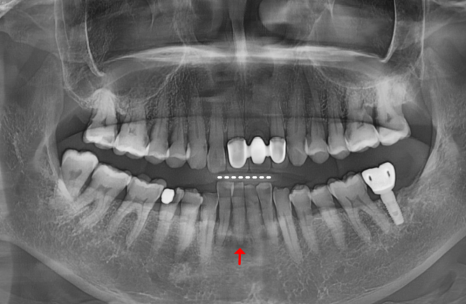

2년 사이 치아가 위로 솟고

200727(왼) 221022 (오)

2년 전만 해도 뼈 상태가 양호하고

흔들림도 없으셨던 분인데,

2년 후 다시 뵙게 된 환자분은

아래 앞니 2개가 눈에 띄게 솟구치고

심하게 흔들리는 상태였습니다.

원인은 뿌리 염증으로

잇몸뼈가 녹아

지지력이 사라진 탓이었는데요.

마치 흙이 쓸려 내려간 나무가 들썩이듯,

뼈가 없으니 치아가 위로 밀려 올라온 것이죠.